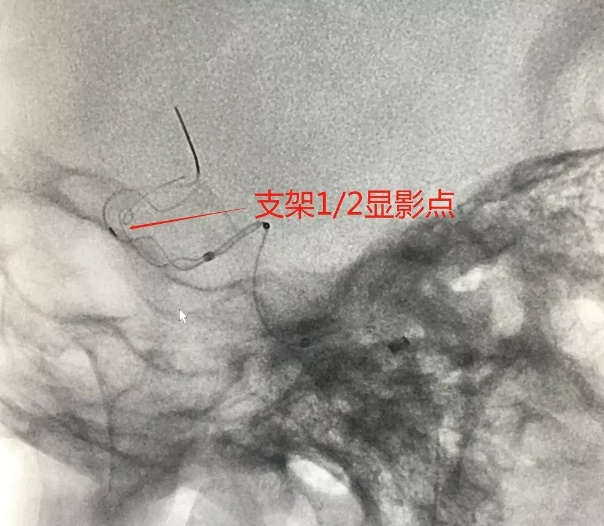

麻醉成功后,患者仰卧,常规消毒,铺巾, Seldinger法穿刺右侧股动脉,置入5F动脉鞘,置入5F造影管行右侧颈内动脉正侧位及3D造影后,更换6F长动脉鞘,6F中间导管在导丝引导下进入右侧颈动脉分叉端并固定。根据3D造影选择工作体位并放大做路图后,T-track微导管在微导丝引导下进入右侧大脑中动脉,经微导管送入4.0×45mm Tubridge®支架,观察 Marker位置后,于颈动脉分叉附近缓慢释放支架。

Tubridge®释放过程

锚定后,整体回撤至合适位置后,通过张力释放法缓慢释放支架,直至支架完全打开。观察见支架贴壁良好,动脉瘤颈完全覆盖,遂完全释放支架。